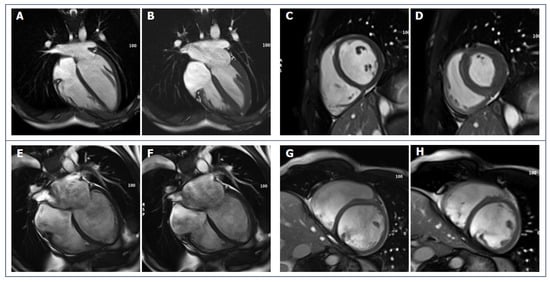

- Czimbalmos, C.; Csecs, I.; Toth, A.; Kiss, O.; Suhai, F.I.; Sydo, N.; Dohy, Z.; Apor, A.; Merkely, B.; Vago, H. The demanding grey zone: Sport indices by cardiac magnetic resonance imaging differentiate hypertrophic cardiomyopathy from athlete’s heart. PLoS ONE 2019, 14, e0211624. [Google Scholar] [CrossRef]